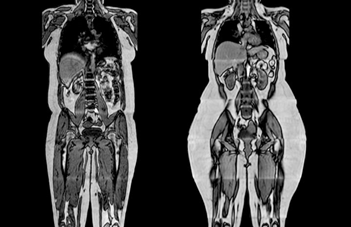

而海豚看人類還有第二個(gè)維度,大概就是這樣的。。。

給你了一個(gè)做實(shí)時(shí)B超

海豚的聲納能夠穿透人體,而同為哺乳動(dòng)物在身體結(jié)構(gòu)上也很相似,這也使得海豚在嗅覺之外分辨人類性別輕而易舉。

海豚發(fā)出的超聲波聲強(qiáng)最大能達(dá)到8W每平方厘米,可以穿適幾十厘米的沙土發(fā)現(xiàn)藏在下面的魚,而我們用B超檢查身體時(shí)的聲強(qiáng)不超過80mW,作為治療用途時(shí)一般也不會(huì)超過2W。所以對于海豚來說,人類的皮膚、肌肉和脂肪等幾乎是適明的.